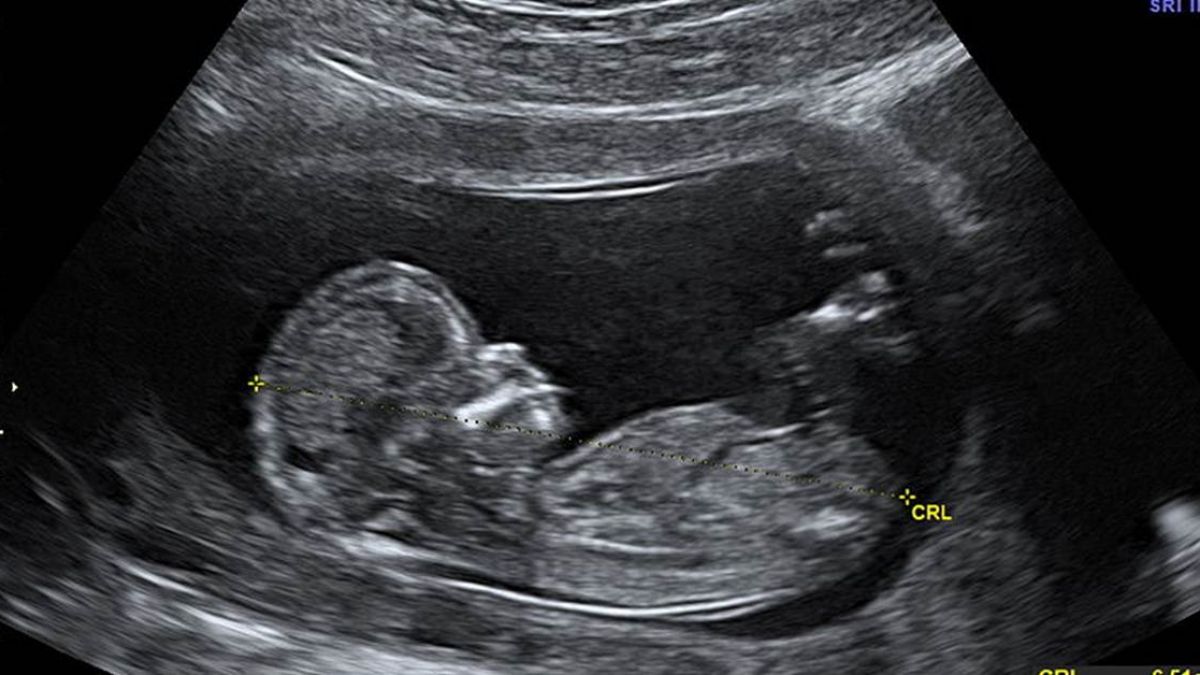

▼護理師呼籲,若要作流產手術,請在小孩6週前處理,不要等小孩變大。(示意圖/翻攝自Pixabay

原PO表示,「我不反對流產,畢竟孩子生下來如果不會養,那只會更慘,但為什麼不早一點呢?」若週數大一點,孩子會哭,不會哭的會動,原PO不少前輩會把孩子放在盒子中,讓他們痛苦的走,原PO則選擇注射一劑麻醉,讓他們好好離開。

原PO沉痛的呼籲,「拜託各位,如果你還沒準備好一切,如果你沒有肩膀負起責任,請你不要懷孕,如果你懷孕了,請你在心跳開始前(6週)到診所、到醫院處理」,希望不幸的孩子能少一點。